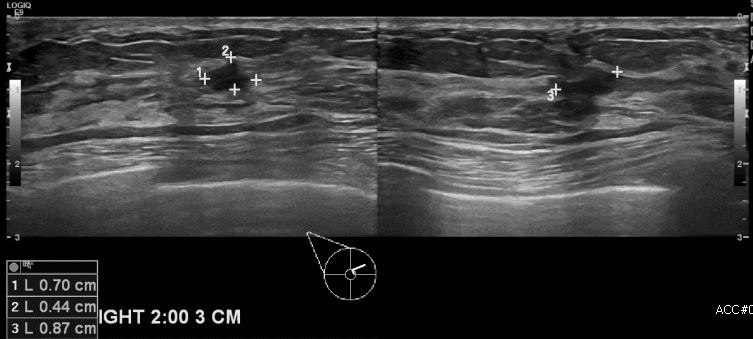

우측 유방통증으로 내원하신 40대 여성분으로 본원 초음파상 우측 2시방향에서 3cm

떨어진 거리의 멍울 조직검사 시행하여 우측 침윤성 유관암 진단 되었습니다.